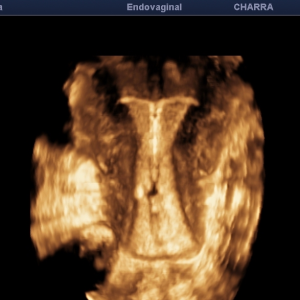

Echographies gynécologiques, Monitorage de l'ovulation (parcours PMA)

Hystérosonographie

Diplômée en Echographie foetale et Gynécologique

Agrément National pour la réalisation des échographies du Premier Trimestre de grossesse